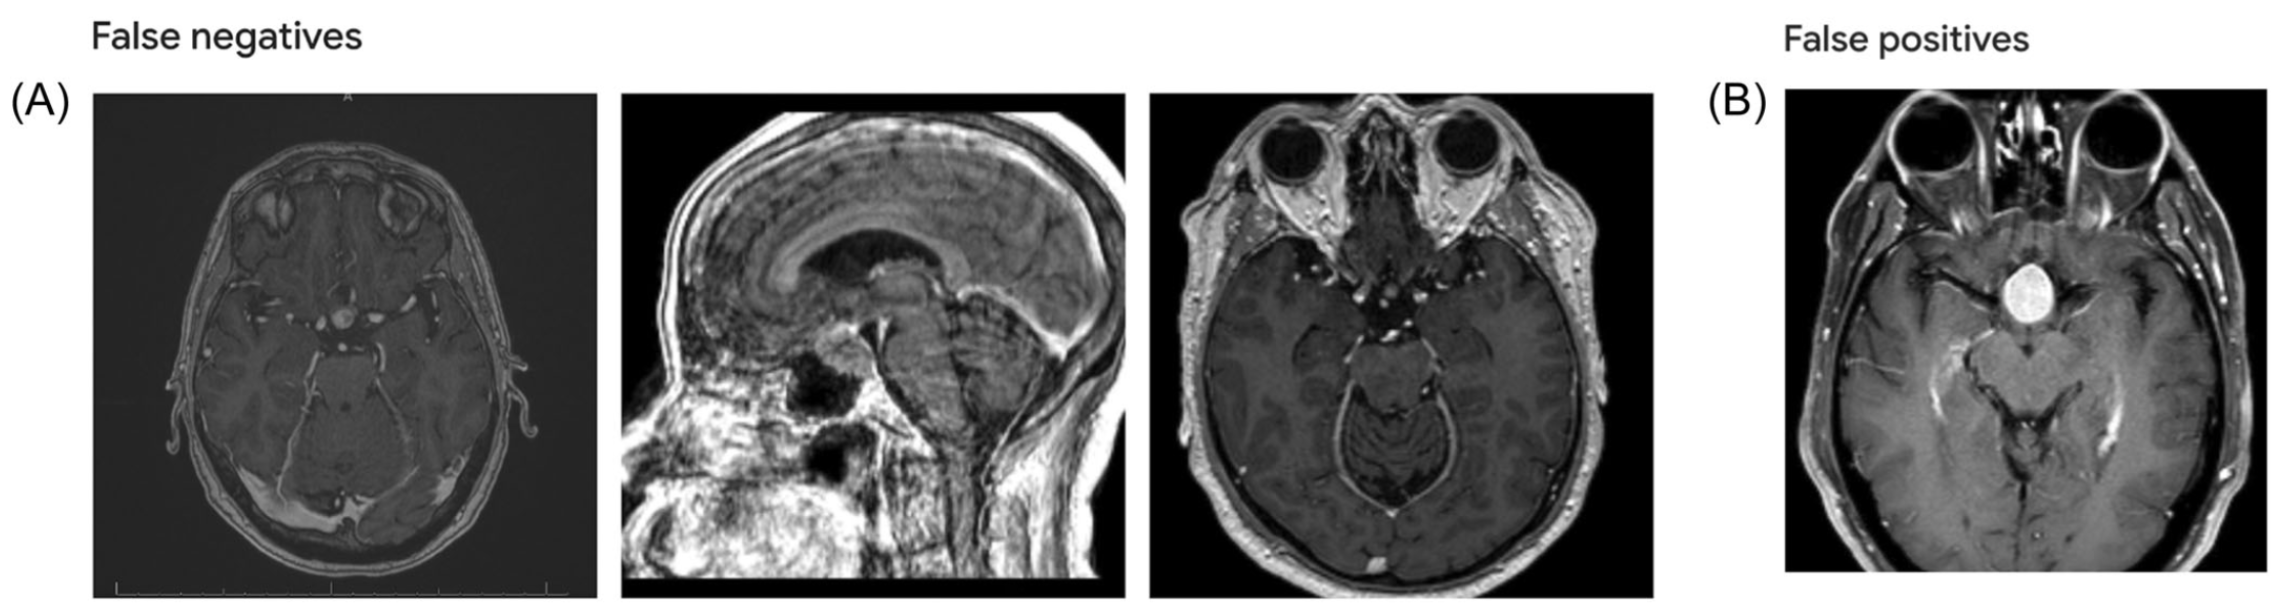

To train the model, the team used 1,628 MRI images from 116 patients. At standard settings, the system correctly classified tumors 97.55% of the time. For pituitary macroadenomas, it reached 97% sensitivity and 98.96% specificity. Sensitivity reflects how well true cases are found. Specificity shows how often false calls are avoided. For parasellar meningiomas, sensitivity stood at 98.41% and specificity at 95.53%.

The researchers then tested the model on 959 new images it had never analyzed. The accuracy held steady. That external test is essential before any tool can be trusted in clinics.